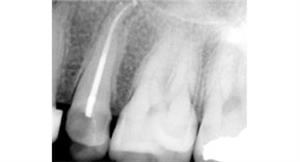

After

A root canal procedure (endodontic treatment) is often required to save an infected tooth. Bacteria can enter a tooth through a cavity or a damaged filling. When this happens, the tooth can become abscessed, meaning the pulp inside the tooth becomes infected. An abscessed tooth can be quite painful and cause swelling in the surrounding gum tissues. If left untreated, it can cause several oral health problems. A root canal procedure removes the infected pulp and any other infected tissues within the tooth.